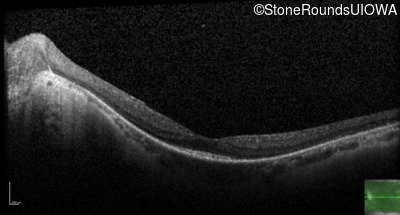

Optical Coherence Tomography - Right - 20/40 +1

Exemplar / OCT Stack